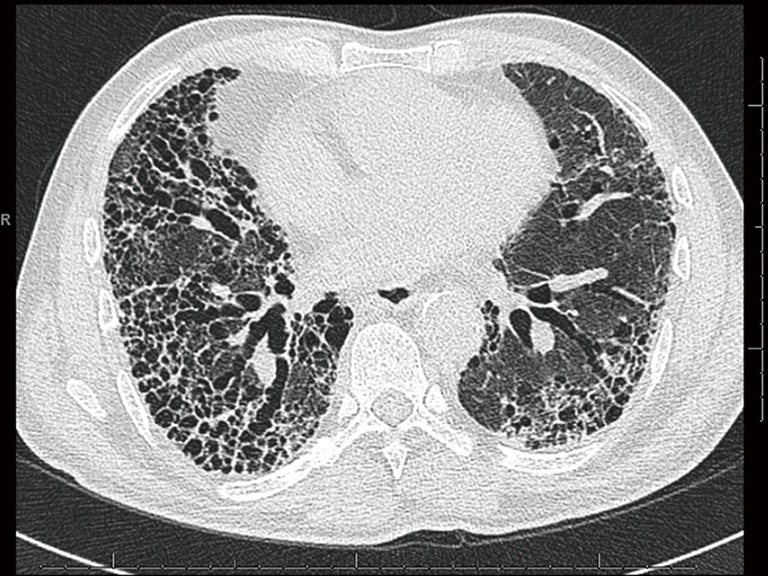

Routine chest radiographs may reveal decreased lung volumes, with prominent reticular interstitial markings, predominantly in the lung bases and lung periphery. High resolution computed tomography (HRCT) of the lungs is required in all cases of suspected IPF, and constitutes an essential component in the diagnosis of the disease. The presence of a definite UIP pattern on HRCT (Table 1), with reticulation, a basal predominance, subpleural honeycombing and traction bronchiectasis or bronchiolectasis (Figure 1), and the absence of features inconsistent with UIP (e.g., upper or middle zone predominance, extensive ground glass opacities, cysts, consolidation or air trapping) enable a multidisciplinary team to make a clinico-radiological diagnosis of IPF in a patient with no other known cause of UIP (1,3). The absence of honeycombing on HRCT, but fulfilling the remaining criteria, should be labelled as probable UIP, and requires histological confirmation.

Figure 1.

An HRCT of the lungs showing the classical UIP pattern: honeycomb transformation, the sub-pleural distribution and traction bronchiectasis can be discerned. HRCT, high resolution computed tomography; UIP, usual interstitial pneumonia.